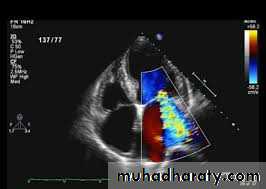

• 8. 2D Echo cardiography - valve

• edema ,mitral regurgitation, LA & LV dilatation,

• pericardial effusion,

• decreased contractility.

Biatrial enlargement

Biventricular dilatation and EF%

Thickened LV (and occasionally RV) wall

Echocardiography